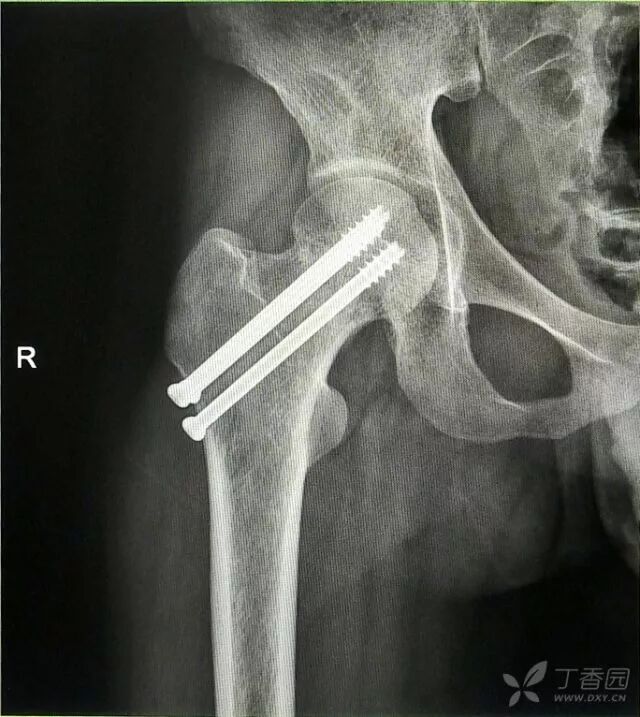

术后复查

术后十个月复查,骨折愈合,正常行走。